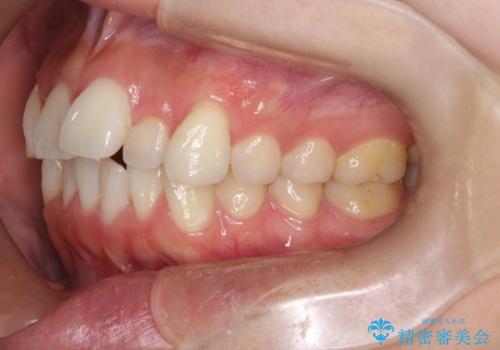

【審美装置】前歯のがたがたを治したい

- 前歯の凸凹と口元の突出感を主訴に来院されました。

臼歯関係が上顎前突傾向のため、上の小臼歯を抜歯してワイヤー矯正を行なっております。

下顎の叢生はIPRを行なって配列しています。